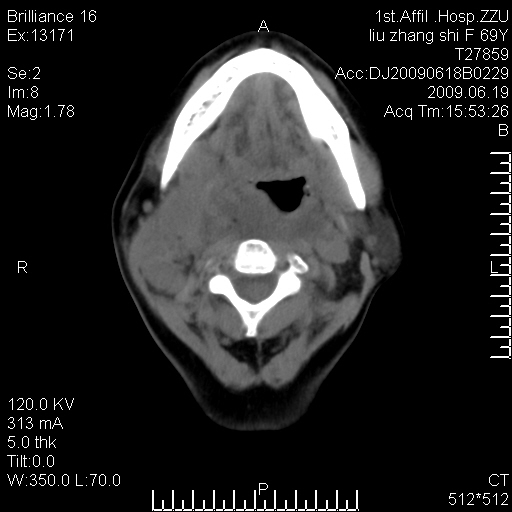

标题: CT26782:女,69岁,颈部占位,3天后公布病理结果。

【病理证实系列】女,69岁,颈部占位,有病理结果,3天后公布。(由于病例时间较久,临床资料不全,请网友见谅)本系列将有几百种常见、少见及罕见病例,均经病理证实。病例资料来自郑州大学第一附属医院。与网友共享,本人有空就发。

甲状腺癌并颈部淋巴结转移。感谢楼主的良苦用心,谢谢。

甲状腺癌并颈部淋巴结转移。

需与鼻咽癌鉴别!

支持甲状腺癌广泛侵及周围结构并颈部淋巴结转移。

鉴别:淋巴瘤、恶性神经源性病变、恶性纤维组织细胞瘤。

病理结果:颈部非霍奇金淋巴瘤。

右侧甲状腺确实有问题